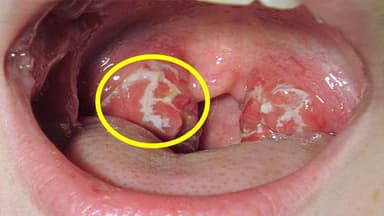

- Nội soi tai mũi họng: qua nội soi có thể cho phép bác sĩ phát hiện những bất thường vùng vòm họng như các vết loét, sủi mùn, khối u…